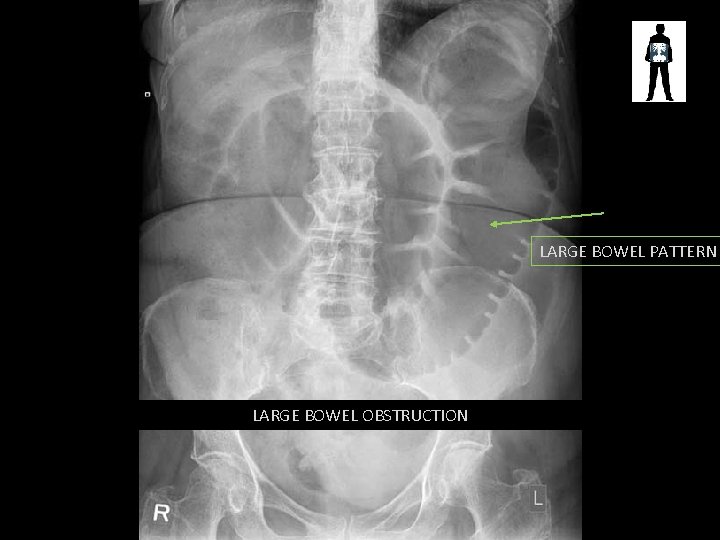

LARGE BOWEL PATTERN LARGE BOWEL OBSTRUCTION